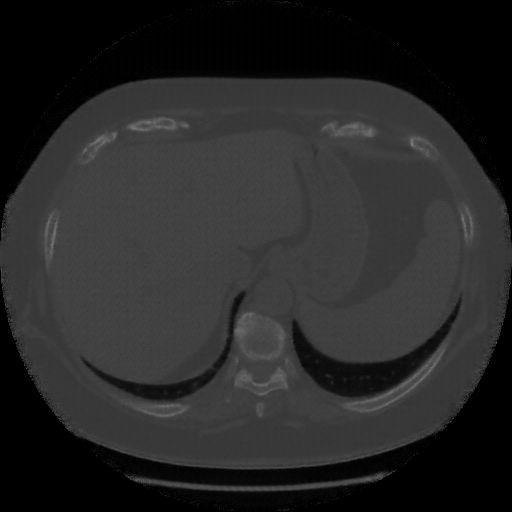

Generated VENOUS CT scan (A→B translation)

Lung window (WL -600, WW 1500 β†’ Low βˆ’1350, High +150)

Mediastinum window (WL 40, WW 400 β†’ Low βˆ’160, High +240)